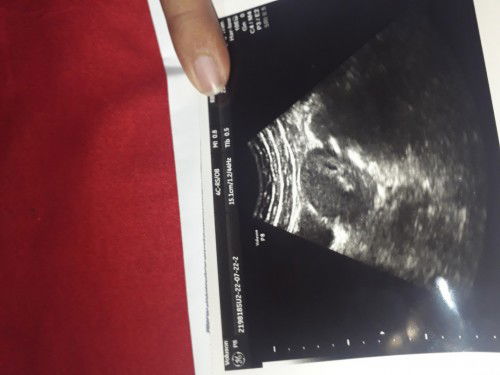

Tanya bunda

Bunda ini lihat (janin) bagaimana ya.. karena wktu usg hnya di sebutkan umurnya aja sekitar 4 / 5wk. Saya hamil anak pertama.#bantusharing #ingintahu

itu sudah terlihat kantong hamilnya bun 😍